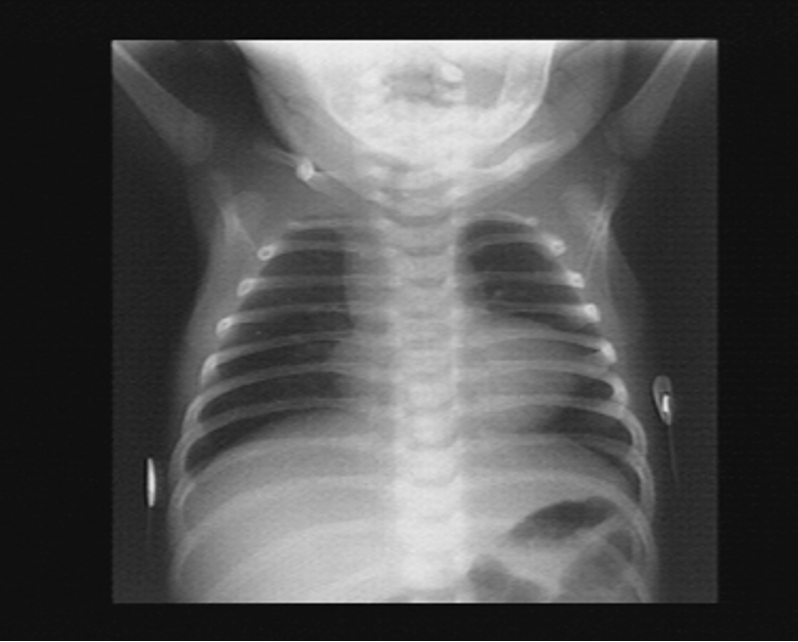

- A chest radiograph: cardiomegaly, narrow mediastinum, and increased pulmonary vasculature. ECG: RAD and RVH

Imaging

- Small to N cardiac silhouette

- Decrease pulmonary vasculature